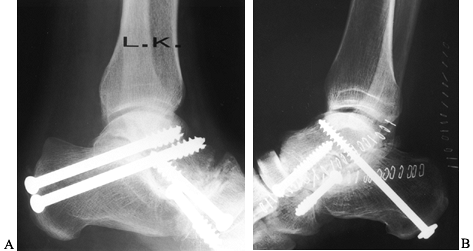

![]() |

Figure 117.21. AP (A) and lateral (B)

radiographs demonstrating ankle arthrodesis in a rheumatoid patient following spontaneous subtalar arthrodesis at an early age. |